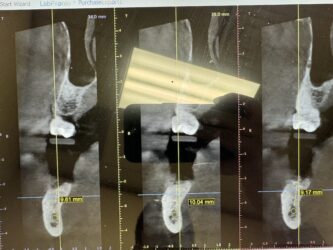

Dr. started the discussion #20, 19 grafting in the forum Implant Tx Planning a year ago

#20 is planned for an extraction. Patient wants to know fixed options so my thought is bridge #20-x-x-18 (not the greatest option due to bone loss on both abutment teeth) or implant #20 and #19. The ridge width around #20 is naturally narrow (6.5-7mm – virtual implant I placed Is 3.5×8.5mm). #20 also has 4mm buccal recession/dehiscence…